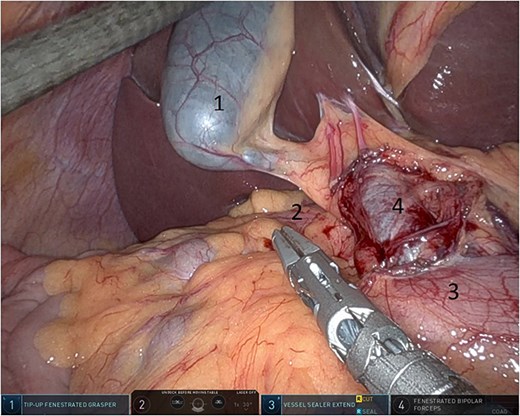

Upon entering the abdominal cavity, dilated bowel loops were observed (Fig. 2), and a significant portion of the colon was found herniated through the foramen of Winslow (Fig. 3). The herniated colon was covered by the pars flaccida (Fig. 4) (Video S1). Careful dissection was performed anterior to the hepatoduodenal ligament (Fig. 5). The gall bladder was retracted to the patient's right upper quadrant, which allowed for the retraction of the foramen of Winslow (Fig. 6) (Video S1). After carefully placing the tip of the instrument posterior to the portal vein and gently elevating it, the herniated colon was successfully reduced (Fig. 7) (Video S1).

Herniated colon through the foramen of Winslow (1: incarcerated colon, 2: hepato-duodenal ligament, 3: herniating colon, 4: the liver).